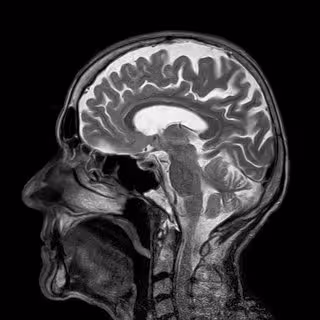

CEREBRO

PIXABAY - Archivo